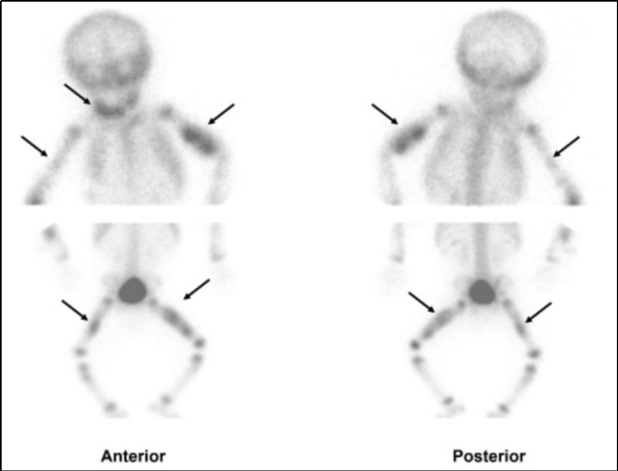

El centellograma óseo mostró áreas de concentración anómala del trazador en maxilar inferior derecho, húmero izquierdo, fémur ipsilateral y, con menor intensidad, en fémur derecho así como distribución irregular en húmero derecho (Fig. 2).

Habitualmente en nuestras instituciones el centellograma esquelético se realiza sin anestesia; se intenta privar antes al niño de sueño, indicándole a la persona cuidadora que lo haga conciliar el sueño inmediatamente antes de adquirir las imágenes. El estudio es de gran utilidad ya que los cambios metabólicos preceden a los anatómicos, visualizándose las fracturas aun cuando estas no presenten signos de reparación radiográfica, así como también la distribución y extensión de las lesiones. En nuestro caso fue útil al permitir identificar el compromiso mandibular no detectado en el examen físico ni radiológico inicial.